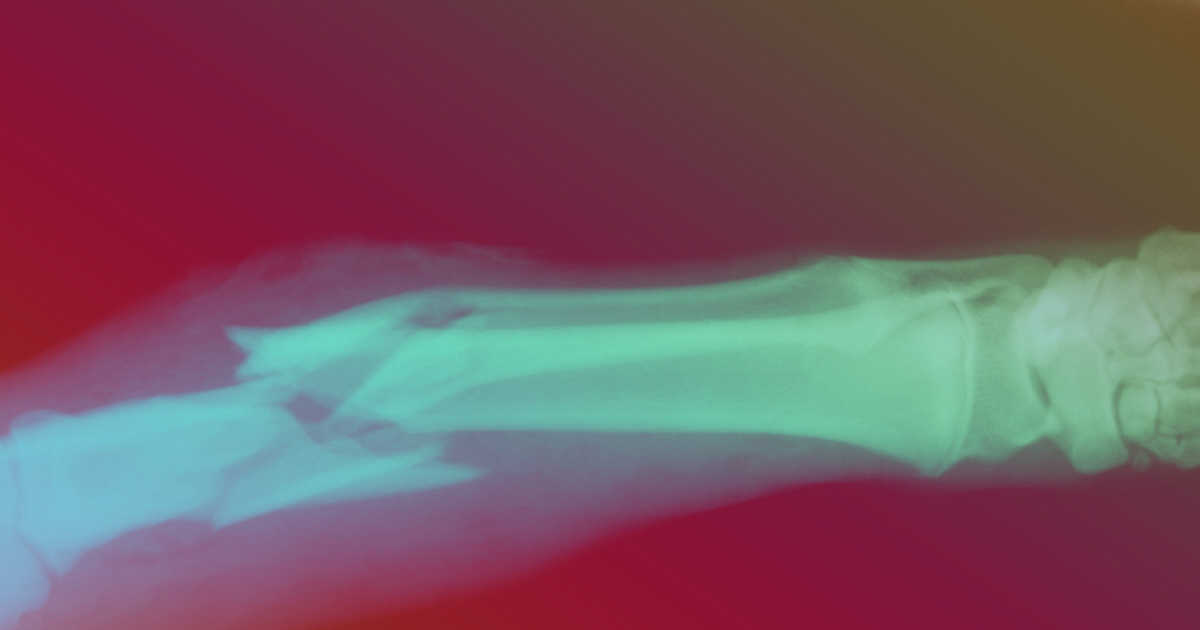

Résultat? Fracture du triquétrum droit.